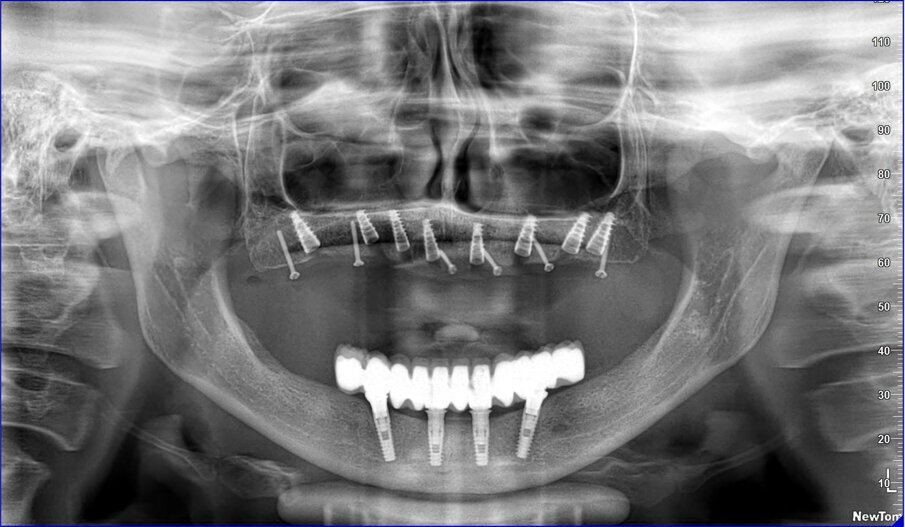

Gli impianti vengono distribuiti lungo tutta l’arcata cercando il parallelismo e limitando il più possibile i cantilever (6-7 impianti superiori e 5-6 impianti inferiori). La scelta di utilizzare i monconi dritti (grazie al parallelismo degli impianti) è da preferire in quanto quest’ultimi sono anche i più robusti e resistenti nel tempo al carico assiale; inoltre caricano l’impianto lungo il suo asse limitando i carichi disassati. Una volta elevato il lembo mucoperiosteo ed evidenziato l’osso alveolare o basale, attenzione deve essere fatta nel fare un’ostectomia riduttiva mediante una fresa a palla del diametro di 0,6-0,8 cm per creare un piano più uniforme possibile tale da formare una piattaforma d’osso alla stessa altezza, guadagnando anche spessore V-L ed uniformità. Gli impianti devono essere posizionati alla stessa altezza tra di loro e distanziati in maniera tale da favorire le manovre di igiene orale inter-implantare. Una volta posizionate le fixture sottocrestali (1-3 mm) come descritto, vanno connessi i monconi solitamente con collare mucoso di 3-4,5 mm in altezza, ponendo particolare attenzione che i tessuti molli suturati non coprano la parte di accoppiamento conometrico. Verificato il parallelismo corretto dei monconi mediante i pin parallelizzatori, siamo certi che l’accoppiamento e la disconnessione delle cappette contenute nella protesi potrà avvenire nel miglior modo possibile senza creare tensioni.

La resina alla stato ancora tenero va indurita con la lampada polimerizzante per alcuni minuti; una volta controllata la masticazione anche senza la chiave articolare e fatti gli opportuni minimi ritocchi, la protesi va rimossa e rifinita a dovere, poi riaccoppiata. Una OPT di conferma serve per verificare il corretto alloggiamento delle cappette sui monconi e la passività del manufatto.

Le tabelle 1-8 mostrano, su un totale di 313 impianti eseguiti tra arcata superiore (208) e inferiore (105), che la tecnica non ha alcuna complicanza biologica a 3 anni di esecuzione, non sono stati evidenziati fallimenti implantari in arcata inferiore (18 pazienti), solamente 5 in arcate superiori tutti nella zona molare (29 pazienti). In 1 paziente è stata registrata una frattura della protesi dovuta a eccessiva distanza tra gli impianti (zona laterale superiore e tuberosità) con antagonista naturale senza presenza di molari; 3 fratture dei denti in pazienti con bruxismo e serramento; circa la metà dei casi (140 impianti) è stata eseguita in condizione post-estrattiva e alcuni casi sono stati caricati con metodiche avanzate di rialzo di seno mascellare (11 pazienti) e 1 con Split Crest. Tutti gli impianti sono stati caricati immediatamente, anche quelli nei settori posteriori superiori o nella tuberosità.